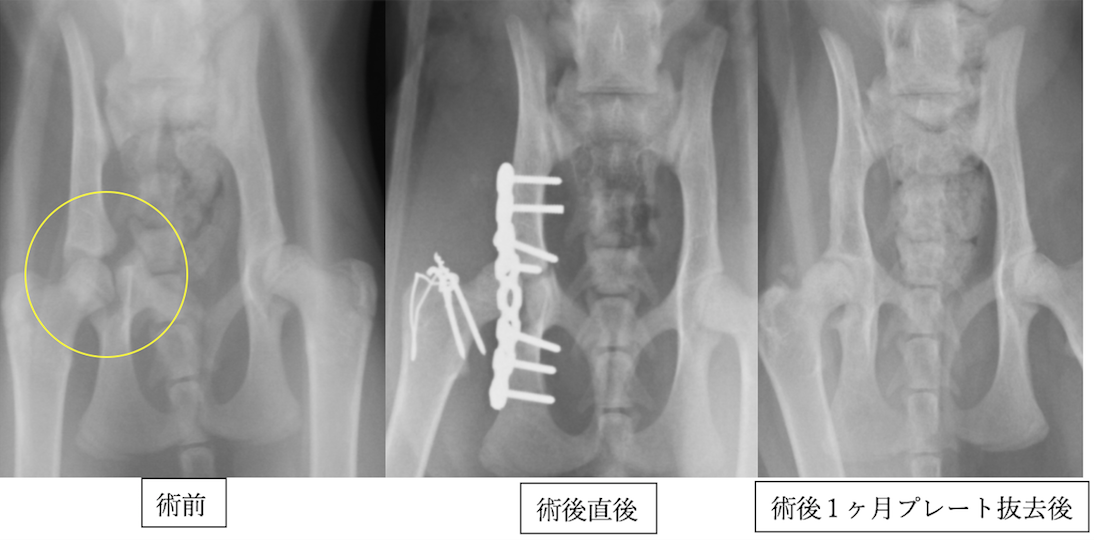

若いノルウェージャンフォレストキャットです。成長阻害することがあるため、プレートとピンは1ヶ月程で抜去しました。術後の経過は順調で、骨折したのがわからないくらい回復しています。